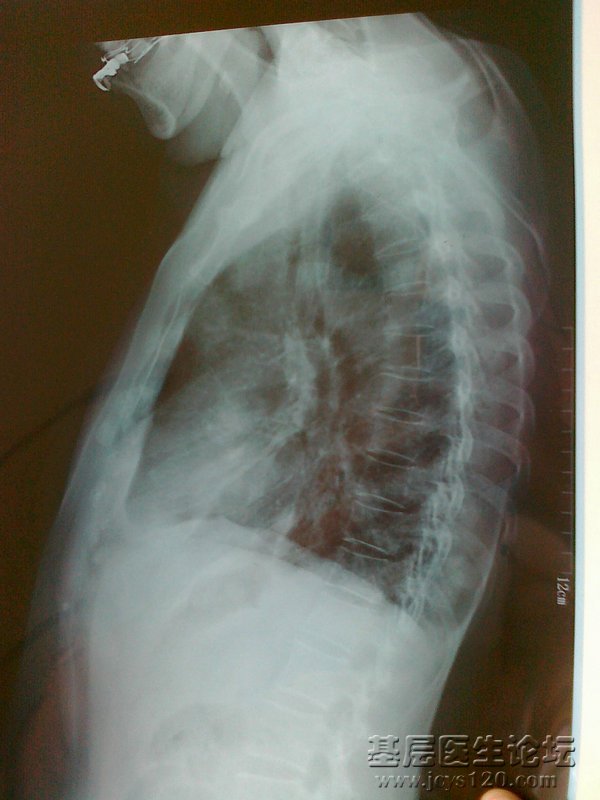

患者,女,67岁,因低热、咳嗽一个月来诊,患者一个月前无明显诱因出现发热、咳嗽,体温在37.5-37.8°c 无寒战、盗汗、乏力。偶有咳白色粘液痰,无胸痛、胸闷,无活动后气喘,在当地门诊输液“青霉素”治疗8天效果不好,发病来饮食,睡眠可,大小便正常,体重无明显变化。

查体:全身浅表淋巴结未触及肿大,双肺叩诊清音,呼吸音粗,未闻及明显干湿啰音,心脏听诊未见明显异常。

胸部CT:双肺多个团块影。 血常规:WBC:13.3×10 9/L 中性粒细胞比率:70.5% HGB:122g/L PLT:259×10 9/L 。